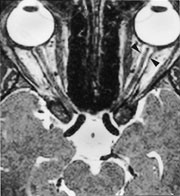

Ved MR-undersøkelse med STIR-frekvens (fettsuppresjon) kan man grunnet økt vanninnhold påvise høysignalområder i aktiv fase i fortykkede muskler (fig 7 a, b). MR kan gi opplysning om muskelkontraktilitet ved repetisjon over flere minutter. Dette kan hjelpe til å oppdage subklinisk sykdom og demonstrerer det naturlige forløpet av sykdommen. Strabismeoperasjon bør utsettes til det ikke påvises noen aktivitet i sykdommen i en eller flere muskler, og botulinumtoksininjeksjon bør unngås hvis muskelen er klart fibrotisk og rigid. Immunsuppressiv behandling bør bare gis ved aktiv sykdom, når inflammasjon er påvist ved STIR-teknikk (9).